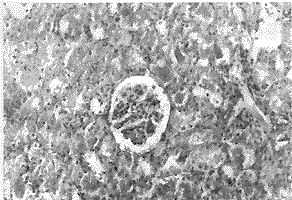

透射电镜下:烫伤后5小时的心肌细胞线粒体肿胀,嵴短而稀疏(照片3)。而TRH治疗组的线粒体上述改变不明显(照片4)。

照片3:NS对照组烫伤后5小时的心肌细胞线粒体肿胀,

嵴短而稀疏。×10000